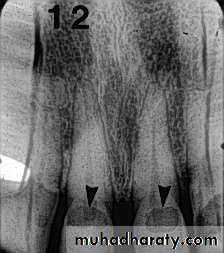

• Radiography

Carious lesions are detectable radiographically when there has been enough demineralization to allow it to be differentiate from normalThey are valuable in detecting proximal caries which may go undetected during clinical examination.

On average they have around 50% to 70% sensitivity in detecting carious lesions.

40% demineralization is required for definitive decision on caries